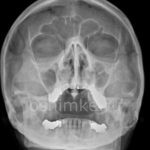

Если воспалительный процесс приводит к заполнению полости жидкостью, которая не может свободно вытекать, то на рентгеновском снимке появляется тень с горизонтальным уровнем.

На этой фотографии отчетливо видно количество жидкости в верхнечелюстных синусах. Медики называют этот рентгеновский эффект «молоко в стакане».

У больного обнаружен гайморит с обеих сторон. Чтобы убедиться в правильности диагноза, проводится рентген в двух проекциях: прямой и боковой. Если на обоих изображениях виден уровень накопившейся жидкости, то диагноз гайморита не подлежит сомнению.

Определить тип скопившейся жидкости – слизь или гной – рентгенолог не в состоянии. Если требуется более детальное исследование всех стенок верхнечелюстных пазух, проводится рентген в трех проекциях: носоподбородочной, подбородочной и аксиальной.

Почти всегда при гайморите на рентгене (фото 6) обнаруживается характерное изображение, напоминающее молоко в стакане: в черных пазухах видно белое инфильтративное содержимое. Рентгеновский снимок пазух носа при гайморите, в сочетании с диагностическими симптомами, помогает врачу поставить правильный диагноз. Однако при скоплении гноя при гайморите (фото внизу страницы), патологические тени округлой формы не наблюдаются.